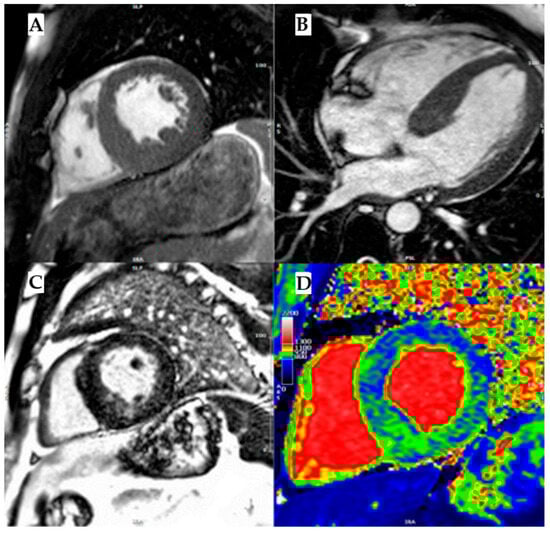

As it is an X-linked disease, men are more commonly affected than women, who show a mild disease phenotype in heterozygosis or because of lyonization. The disease incidence is estimated at one case per 50,000–100,000 people. Early signs and symptoms usually manifest during childhood and adolescence in patients with the severe form of Fabry disease (men or women in homozygosis) and may include neuropathic pain with a disto-proximal progression, autonomic dysfunction, gastro-intestinal complaints, angiokeratomas, and hypohidrosis. These precede the development of kidney dysfunction and cardiac and cerebrovascular complications in adulthood, which cause poor quality of life and an increased risk of premature death. However, clinical red flags are often recognized late, and diagnosis is not uncommon in patients with advanced disease manifestations such as kidney insufficiency under dialysis treatment, heart failure, or ischemic ictus. Cardiac manifestations are common in Fabry disease, occurring in 40–60% of patients. The classic cardiac involvement is a concentric left ventricular hypertrophy, but it can also present as asymmetrical septal or obstructive. The age of onset for full cardiac involvement is strictly dependent on the level of residual AGAL-A activity related to the genetic variant. In men, hypertrophy develops usually after the third or fourth decade of life, while in women the onset of cardiomyopathy is delayed by 10 years [36]. CMR typically shows LGE in the basal inferolateral wall and low native T1 caused by fat deposits (Figure 6).

Figure 6. Fabry disease. (A) Mid-ventricular short axis cine-bSSFP image in telediastole and (B) cine-bSSFP 4- chamber image in telediastole, both showing a case of Anderson–Fabry disease with asymmetric septal LV hypertrophy. (C) Mid-ventricular short axis late gadolinium enhancement (LGE) image showing mid-wall LGE in inferoseptum and inferior wall. (D) Mid-ventricular short axis T1 map showing a diffuse reduction in intra-myocardial T1 values, with T1 pseudo-normalization in segments with LGE. Reproduced with permission from Licordari, R. J. Clin. Med. 2023 [11].